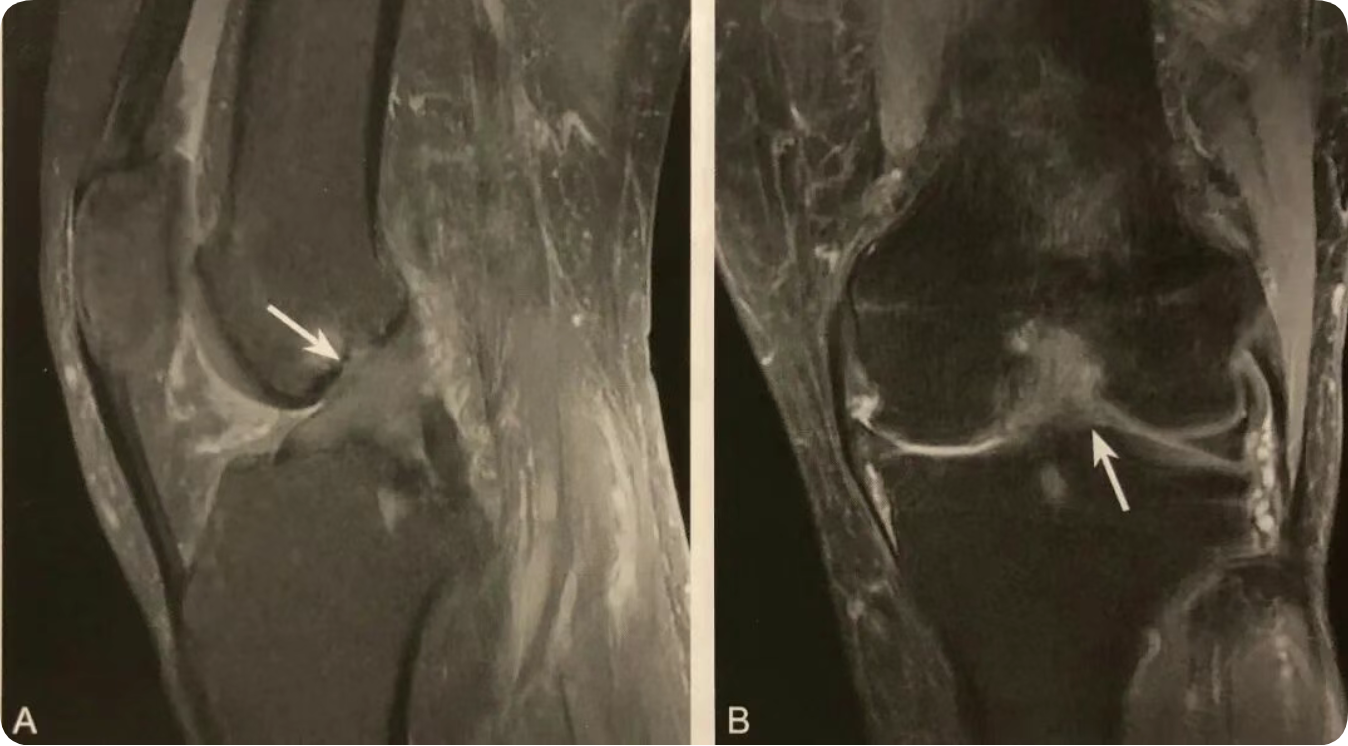

1. 半月板移位的直接征象;

2. 在膝关节 MRI 冠状位半月板体部的中央平面观察;

3. 半月板外缘超过胫骨平台关节面边缘 ≥3mm ;

4. 常伴半月板复杂撕裂或膝关节支持系统损伤,应注意观察。